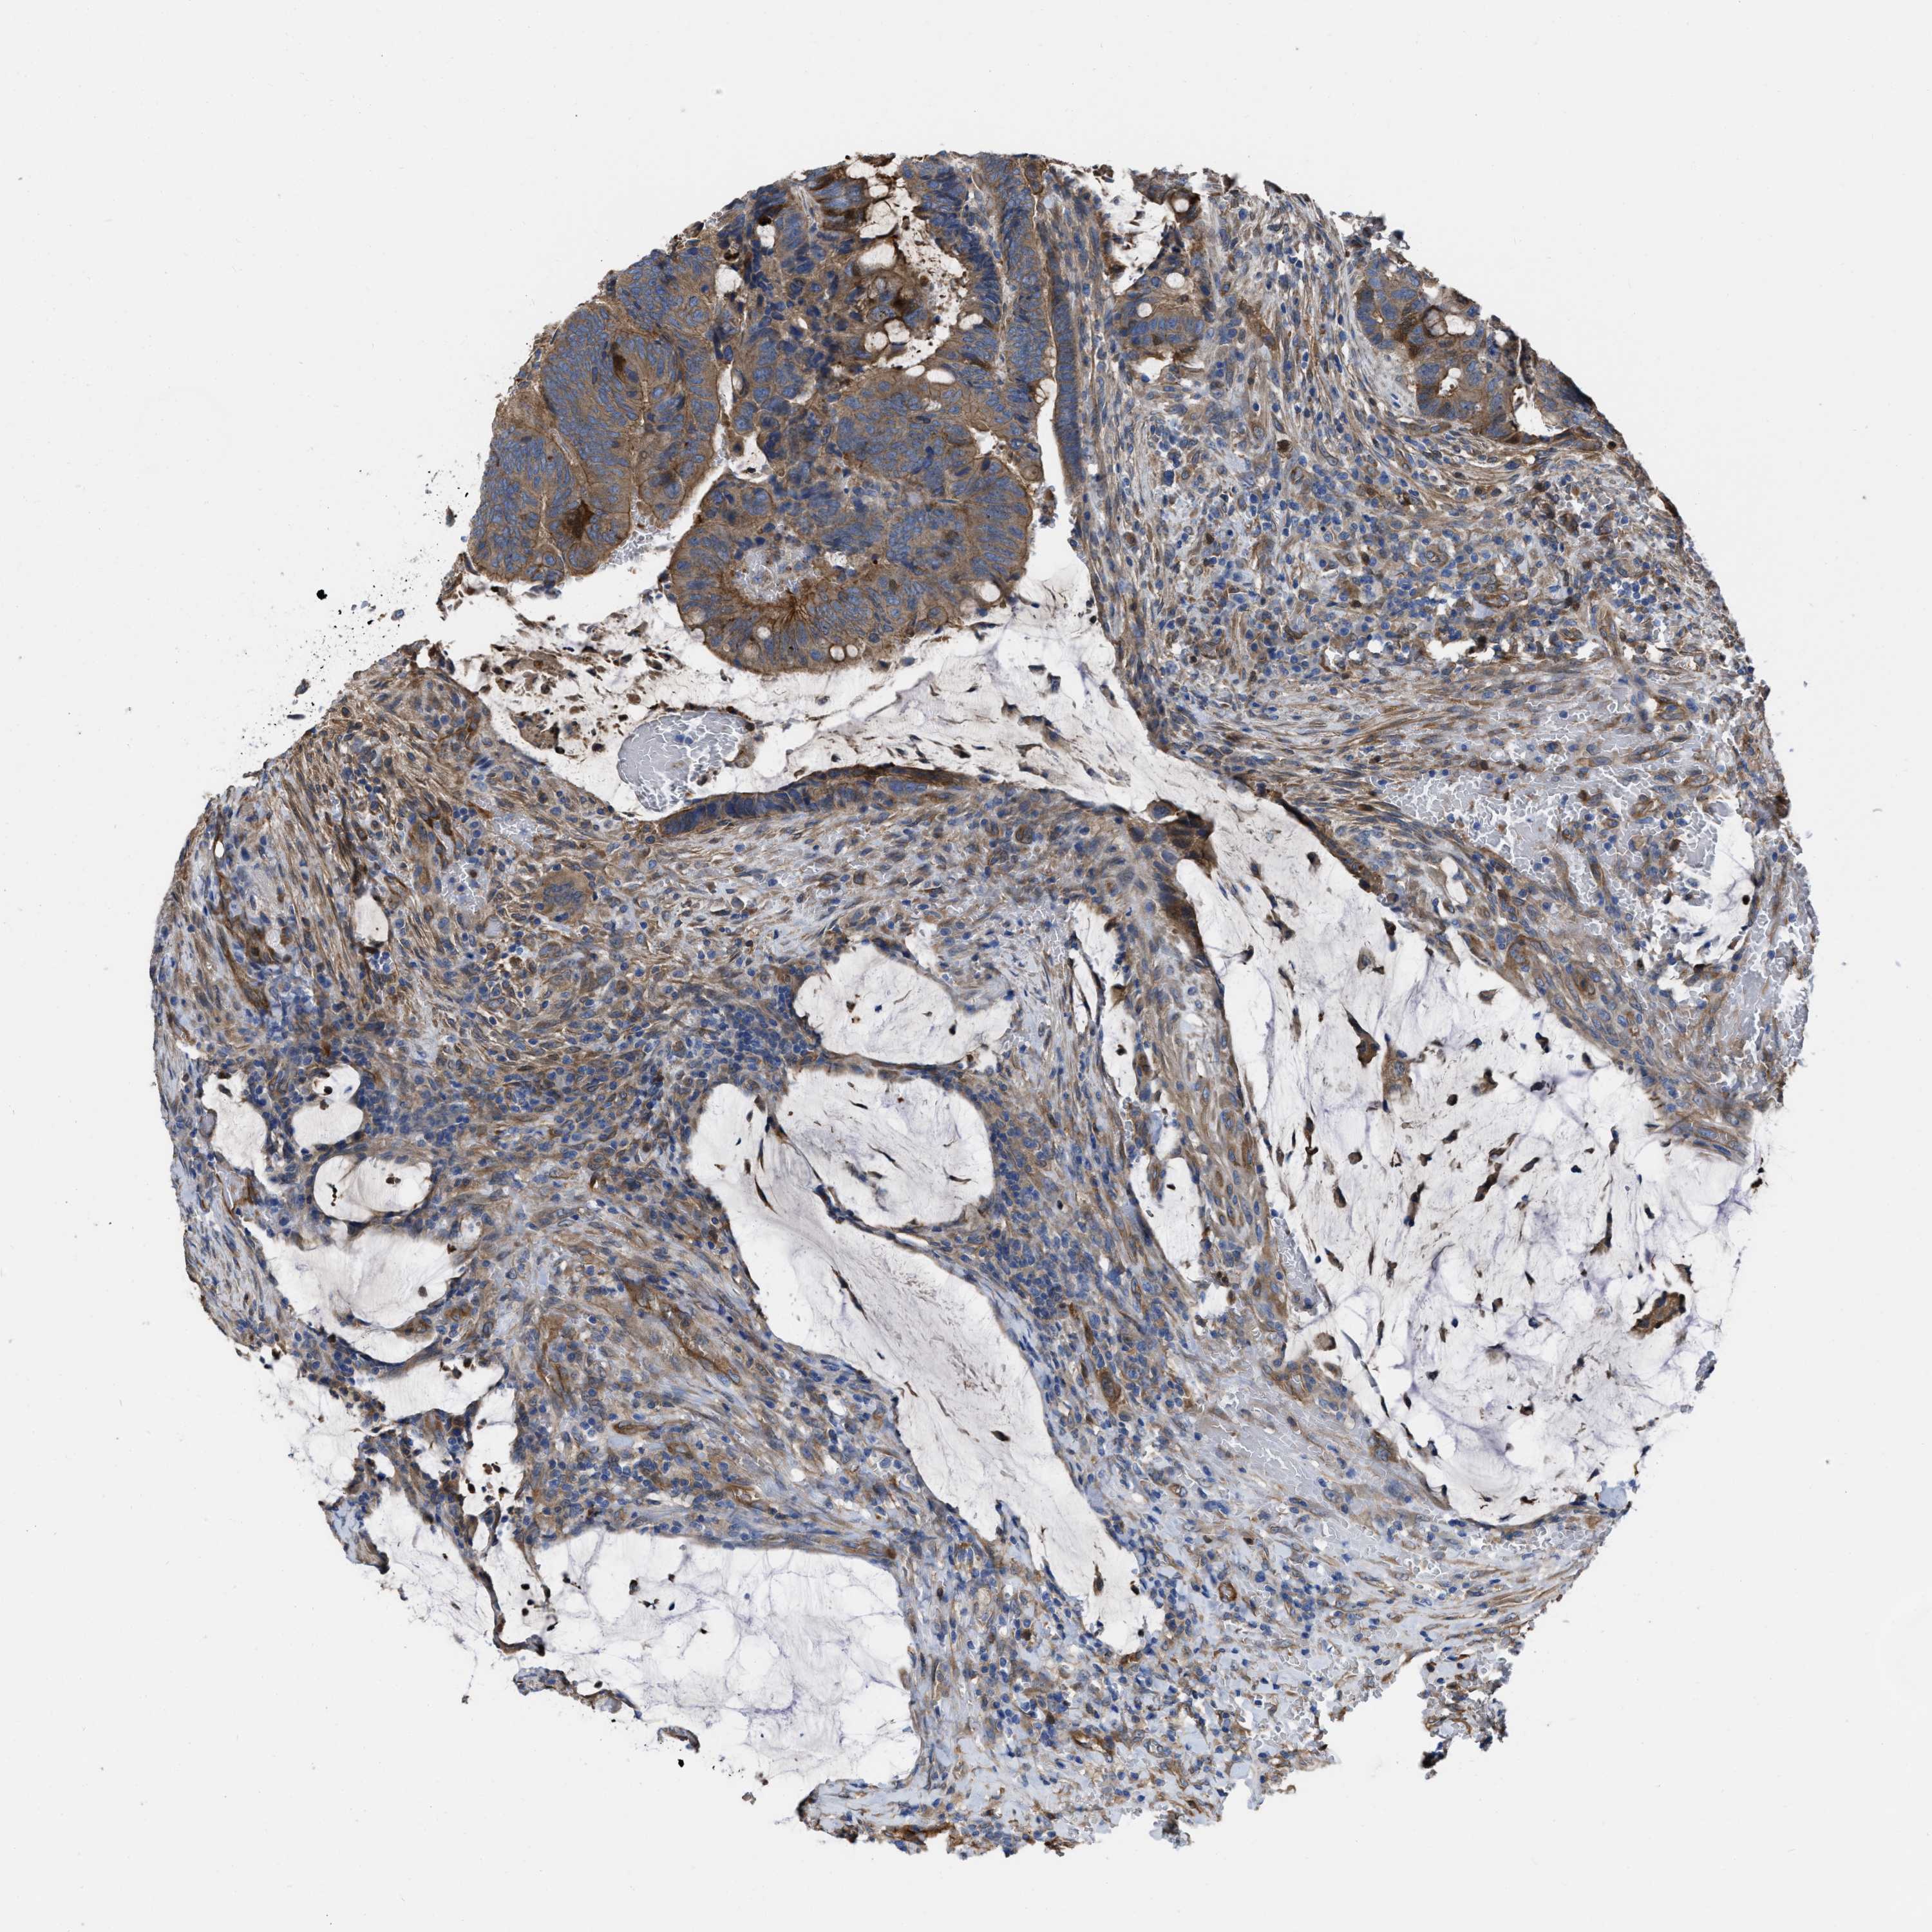

CANCER COLORECTAL CANCER Show tissue menu

Colorectal cancer

Human cancer

Colon adenocarcinoma

Rectum adenocarcinoma